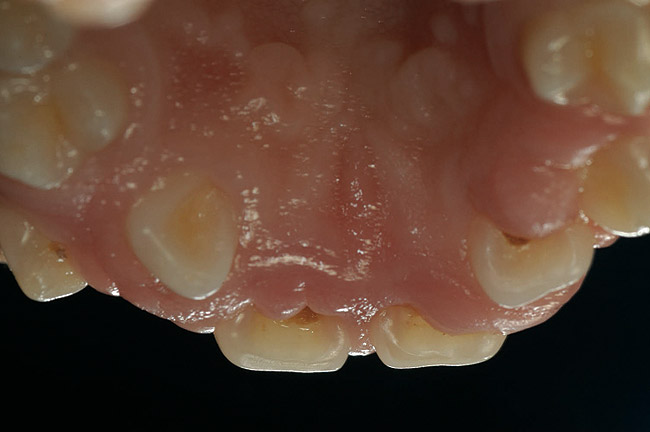

Finally, it must be noted that the psychological and emotional impact of gingival overgrowth receives no or little attention. As increasing numbers of pediatric patients are affected by systemic disease-associated gingival overgrowth, concern should be shown for how pediatric patients interpret what is happening to them and how affected children manage difficulties associated with facial appearance (Figure 1, Figure 2, Figure 3 and Figure 4).

Figure 2  Heart transplant-associated gingival enlargement in a 16-year-old girl. Palatal view.

Figure 2

In patients undergoing immunosuppressive therapy, the prevalence of cyclosporine-associated gingival overgrowth has been found to vary from 25% to 81%.14 In pediatric patients receiving cyclosporine A for more than 3 months, the incidence of disfiguring gingival overgrowth can approach 70%.15 Gingival overgrowth, particularly around maxillary central incisors, is common in transplant patients and the overgrowth can displace maxillary incisors and destroy anterior papillae. The damage results in extensive treatment needs and presents a challenge to traditional therapeutic periodontal approaches. A further concern is the ability of viruses, such as human cytomegalovirus, to replicate in the pockets developed from the excessive gingiva. The author and his colleagues16 detected 68.4% gingival overgrowth in adult renal transplant patients and provided evidence for a link between cytomegalovirus, gingival overgrowth, and renal transplant complications.

Facial differences can bring stigma upon children and adolescents, affect their psychosocial development, self-esteem, and quality of life.35 Because of the centrality of the face, the mouth, and a smile in human interactions, the effect of gingival overgrowth on the smiles of thousands of children cannot be minimized. Regrettably, the media and public culture place a huge value on physical appearance, which can result in a lack of opportunity for and acceptance of those who look different.36 Reports of perception of physical appearance and social alienation suggest that children with facial differences undergo serious psychological and emotional problems as a result of the feelings of isolation and powerlessness.37 Because gingival overgrowth is a visible facial feature it can be categorized as a facial difference. Therefore, by extrapolation, the studies cited35-37 support that human relationships and interaction are negatively influenced by the appearance of gingival overgrowth. Life can be only the sum of moments, and moments lost to pain and suffering that are psychological or social in nature can mean as much or more than moments lost to physical pain and suffering.